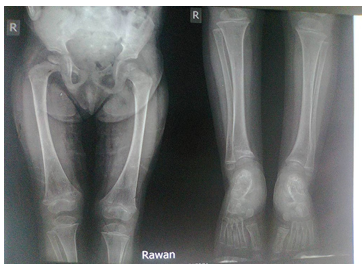

Old radiographs of the younger sister showed osteopenia, fracture in the upper limb, and progressive bowing with no rachitic changes. Figure-3A and 3B show lower limb radiographs showing progressive bowing. Figure-4 (A, B, C, and D) show recent bone radiographs of the younger sister taken during May, 2023 which showed osteopenia, bowing with no rachitic changes. Radiograph of the pelvis showed mild protrusio acetabula (Figure-4A). Radiograph of the wrist showed no rachitic changes (Figure-4B). Radiograph of the lower limbs showed bowing, cortical thinning with scanty spongiosa (Figure- 4C). Lateral skull radiographs showed platybasia (Figure-4D).

Figure-4A: Radiograph of the pelvis showing mild protrusio acetabula

Figure-4B: Radiograph of the wrist showing no rachitic changes

Figure-4C: Radiograph of the lower limbs showing bowing, cortical thinning with scanty spongiosa

Figure-4D: Lateral skull radiographs showed platybasia